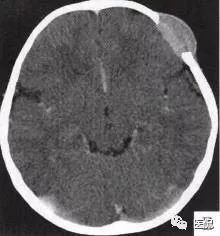

颅脑CT示:图A〜D,CT平扫示左侧额骨、蝶骨见溶骨性骨质缺损,边界清晰,周围无硬化边,伴有软组织肿块向脑外生长,边缘光滑,脑内无明显侵犯;

图H,为颅骨容积重建,提示类圆形骨质缺损,边缘光滑、整齐。